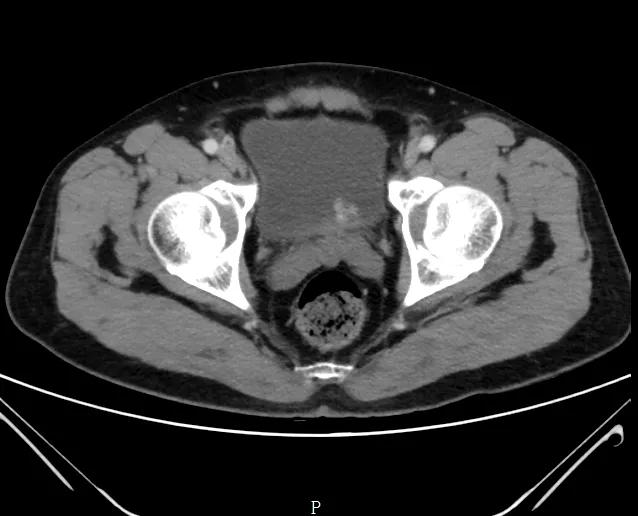

2天后就再次来院办理了住院手续,检查了泌尿系CT增强

泌尿系CT增强结果:

果然有存在“膀胱肿瘤”